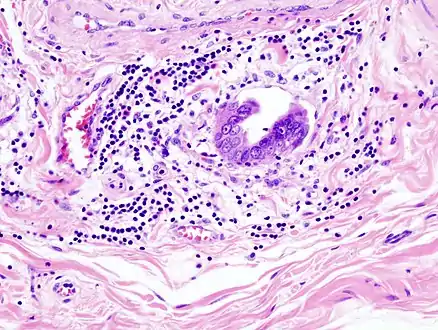

Most tumors are adenocarcinomas, with a small percent being squamous cell carcinomas.